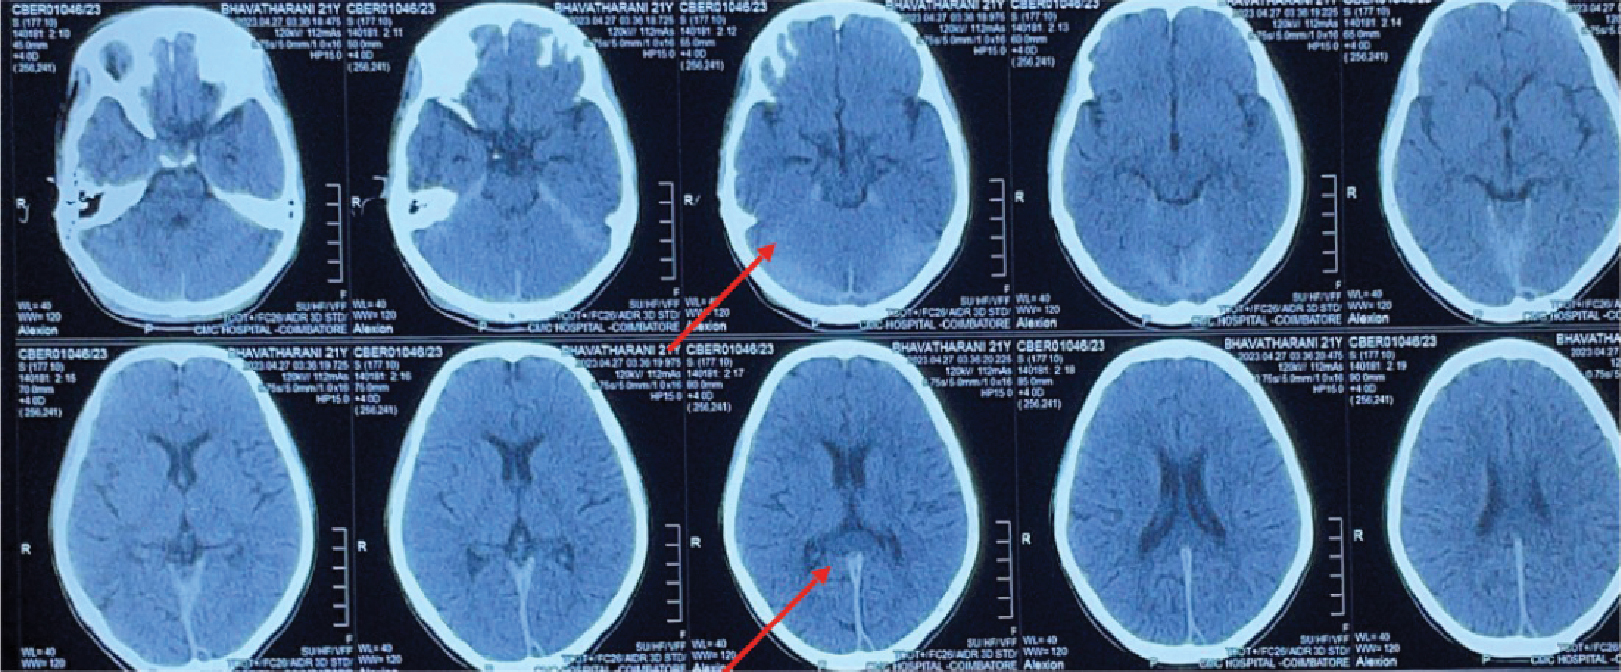

acid amplification test (CBNAAT) and adenosine deaminase (ADA). Noncontrast CT

brain revealed thickened, hyperdense dura along the tentorium (Fig. 3). The contrast-enhanced

Figure 3. Noncontrast CT brain showing thickened hyperdense dural

along posterior falx and tentorium.